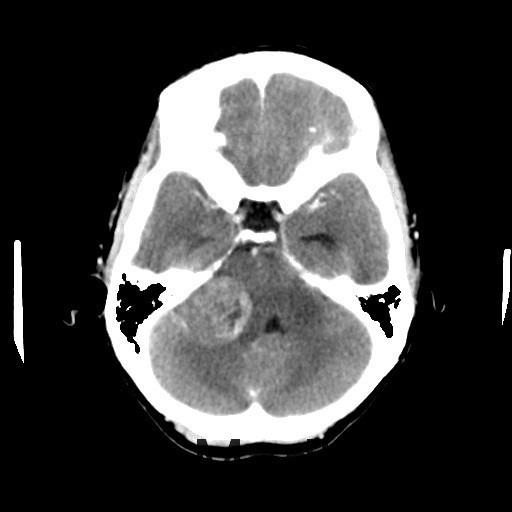

主诉:双眼视物模糊2月余 病史:中年女性,慢性病程。2月前无明显诱因出现双眼视物模糊,当地医院MRI提示:右侧桥小脑角处异常信号,占位,脑膜瘤?胶质瘤?血管母细胞瘤?建议增强扫描。

查体:神志清醒,查体合作。双眼视物模糊,眼球运动无明显异常。双侧瞳孔等大等圆,直径3mm,对光反射灵敏。 辅查:头部CT示:右侧桥小脑角区占位,考虑听神经瘤可能,并梗阻性脑积水。建议进一步MRI检查;头部MR示:右侧桥小脑角区占位,考虑为听神经瘤,并梗阻性脑积水;DTI示脑桥、桥臂及右侧桥小脑角白质纤维束受压移位。

这段:右侧听神经瘤 治疗:完善术前检查,于全麻下行显微镜下右侧乙状窦后入路桥小脑角占位病变切除术+脑室外引流+颅内压探头植入术,术后患者恢复良好,伤口已拆线,无明显红肿不适

随访:术后病理结果提示:(右侧桥小脑角处肿物)肿瘤由梭形细胞构成,可见疏区及密切,部分细胞呈栅栏状排列,细胞有异型性,核分裂可见,间质有散在淋巴细胞浸润,结合免疫组化结果,符合神经鞘瘤。 讨论:听神经瘤是桥小脑区最常见的肿瘤,也是最常见的脑神经瘤,绝大多数病理类型为神经鞘瘤。下面结合本例影像学习一下其影像表现:首先就是部位,发生于桥小脑区的占位第一反应是听神经瘤,而且和岩骨是呈锐角相交,该征象可以和发生于该部位脑膜瘤鉴别。另外,肿瘤沿听神经长如,导致内听道扩大也是一个重要征象。增强扫描可见明显强化,这可以和发生于该部位的胆脂瘤鉴别。